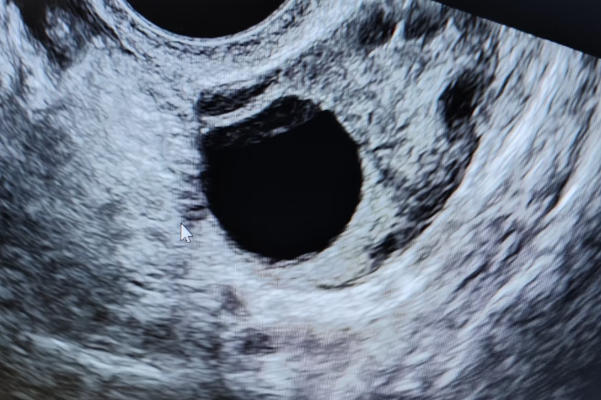

在试管婴儿治疗中,通常期望通过促排卵获得多个卵泡,以增加优质胚胎的生成机会。然而,当仅有一个卵泡发育成熟时,是否能够进行移植?答案是肯定的。临床研究表明,即使只有一个卵泡,只要其质量良好,仍有可能成功受精并发育成优质胚胎。这提示卵泡数量并非绝对限制因素,关键在于卵子的质量与后续胚胎的发育潜力。

一个卵泡做试管的成功率受多重因素影响,其中女性年龄与卵子质量尤为关键。年轻女性(如35岁以下)的卵巢功能相对较好,卵子质量较高,即使只有一个卵泡,其受精率和胚胎发育潜力也显著优于高龄女性。此外,子宫内膜的容受性、激素水平以及生殖中心的技术水平同样重要。这些因素共同作用,使得成功率呈现出个体差异,而非单一数值所能概括。

研究表明,在理想条件下(如卵子质量高、子宫环境良好),成功率可达20%-40%。然而,这一比例会因患者年龄、病因及医疗条件而波动。临床案例中,不乏单卵泡移植成功的报道,但这类案例相对罕见,且多依赖于严格的医疗监控与患者配合。这些数据与案例提醒我们,成功率虽可量化,但实际结果需结合个体情况综合评估。